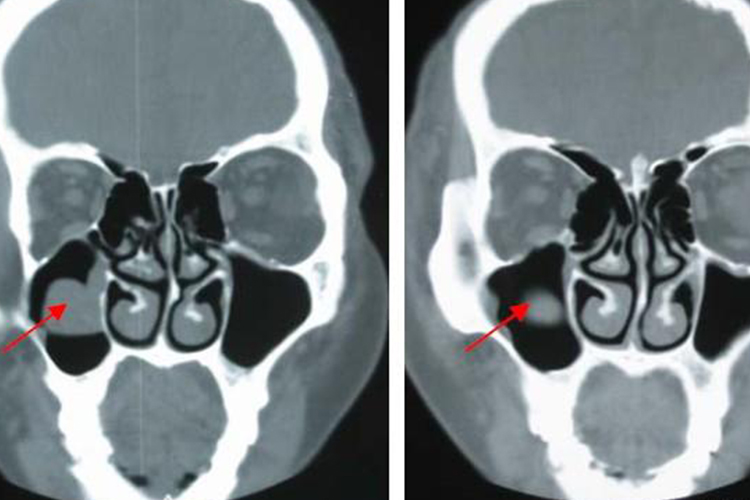

上颌窦黏膜囊肿是一种较为常见的鼻窦疾病,通常由上颌窦黏膜的局部炎症反应导致黏膜腺体分泌物积聚形成,此类囊肿大多为非肿瘤性病变,通常不会自行消退,但也不属于恶性病变。大多数情况下并不严重,但是若未得到及时处理,囊肿增大可能压迫周围结构,引起较为严重的并发症,如感染扩散、视力障碍等。

- 手术治疗:对于症状明显的囊肿,采用内窥镜下囊肿摘除术或窦口开放术。